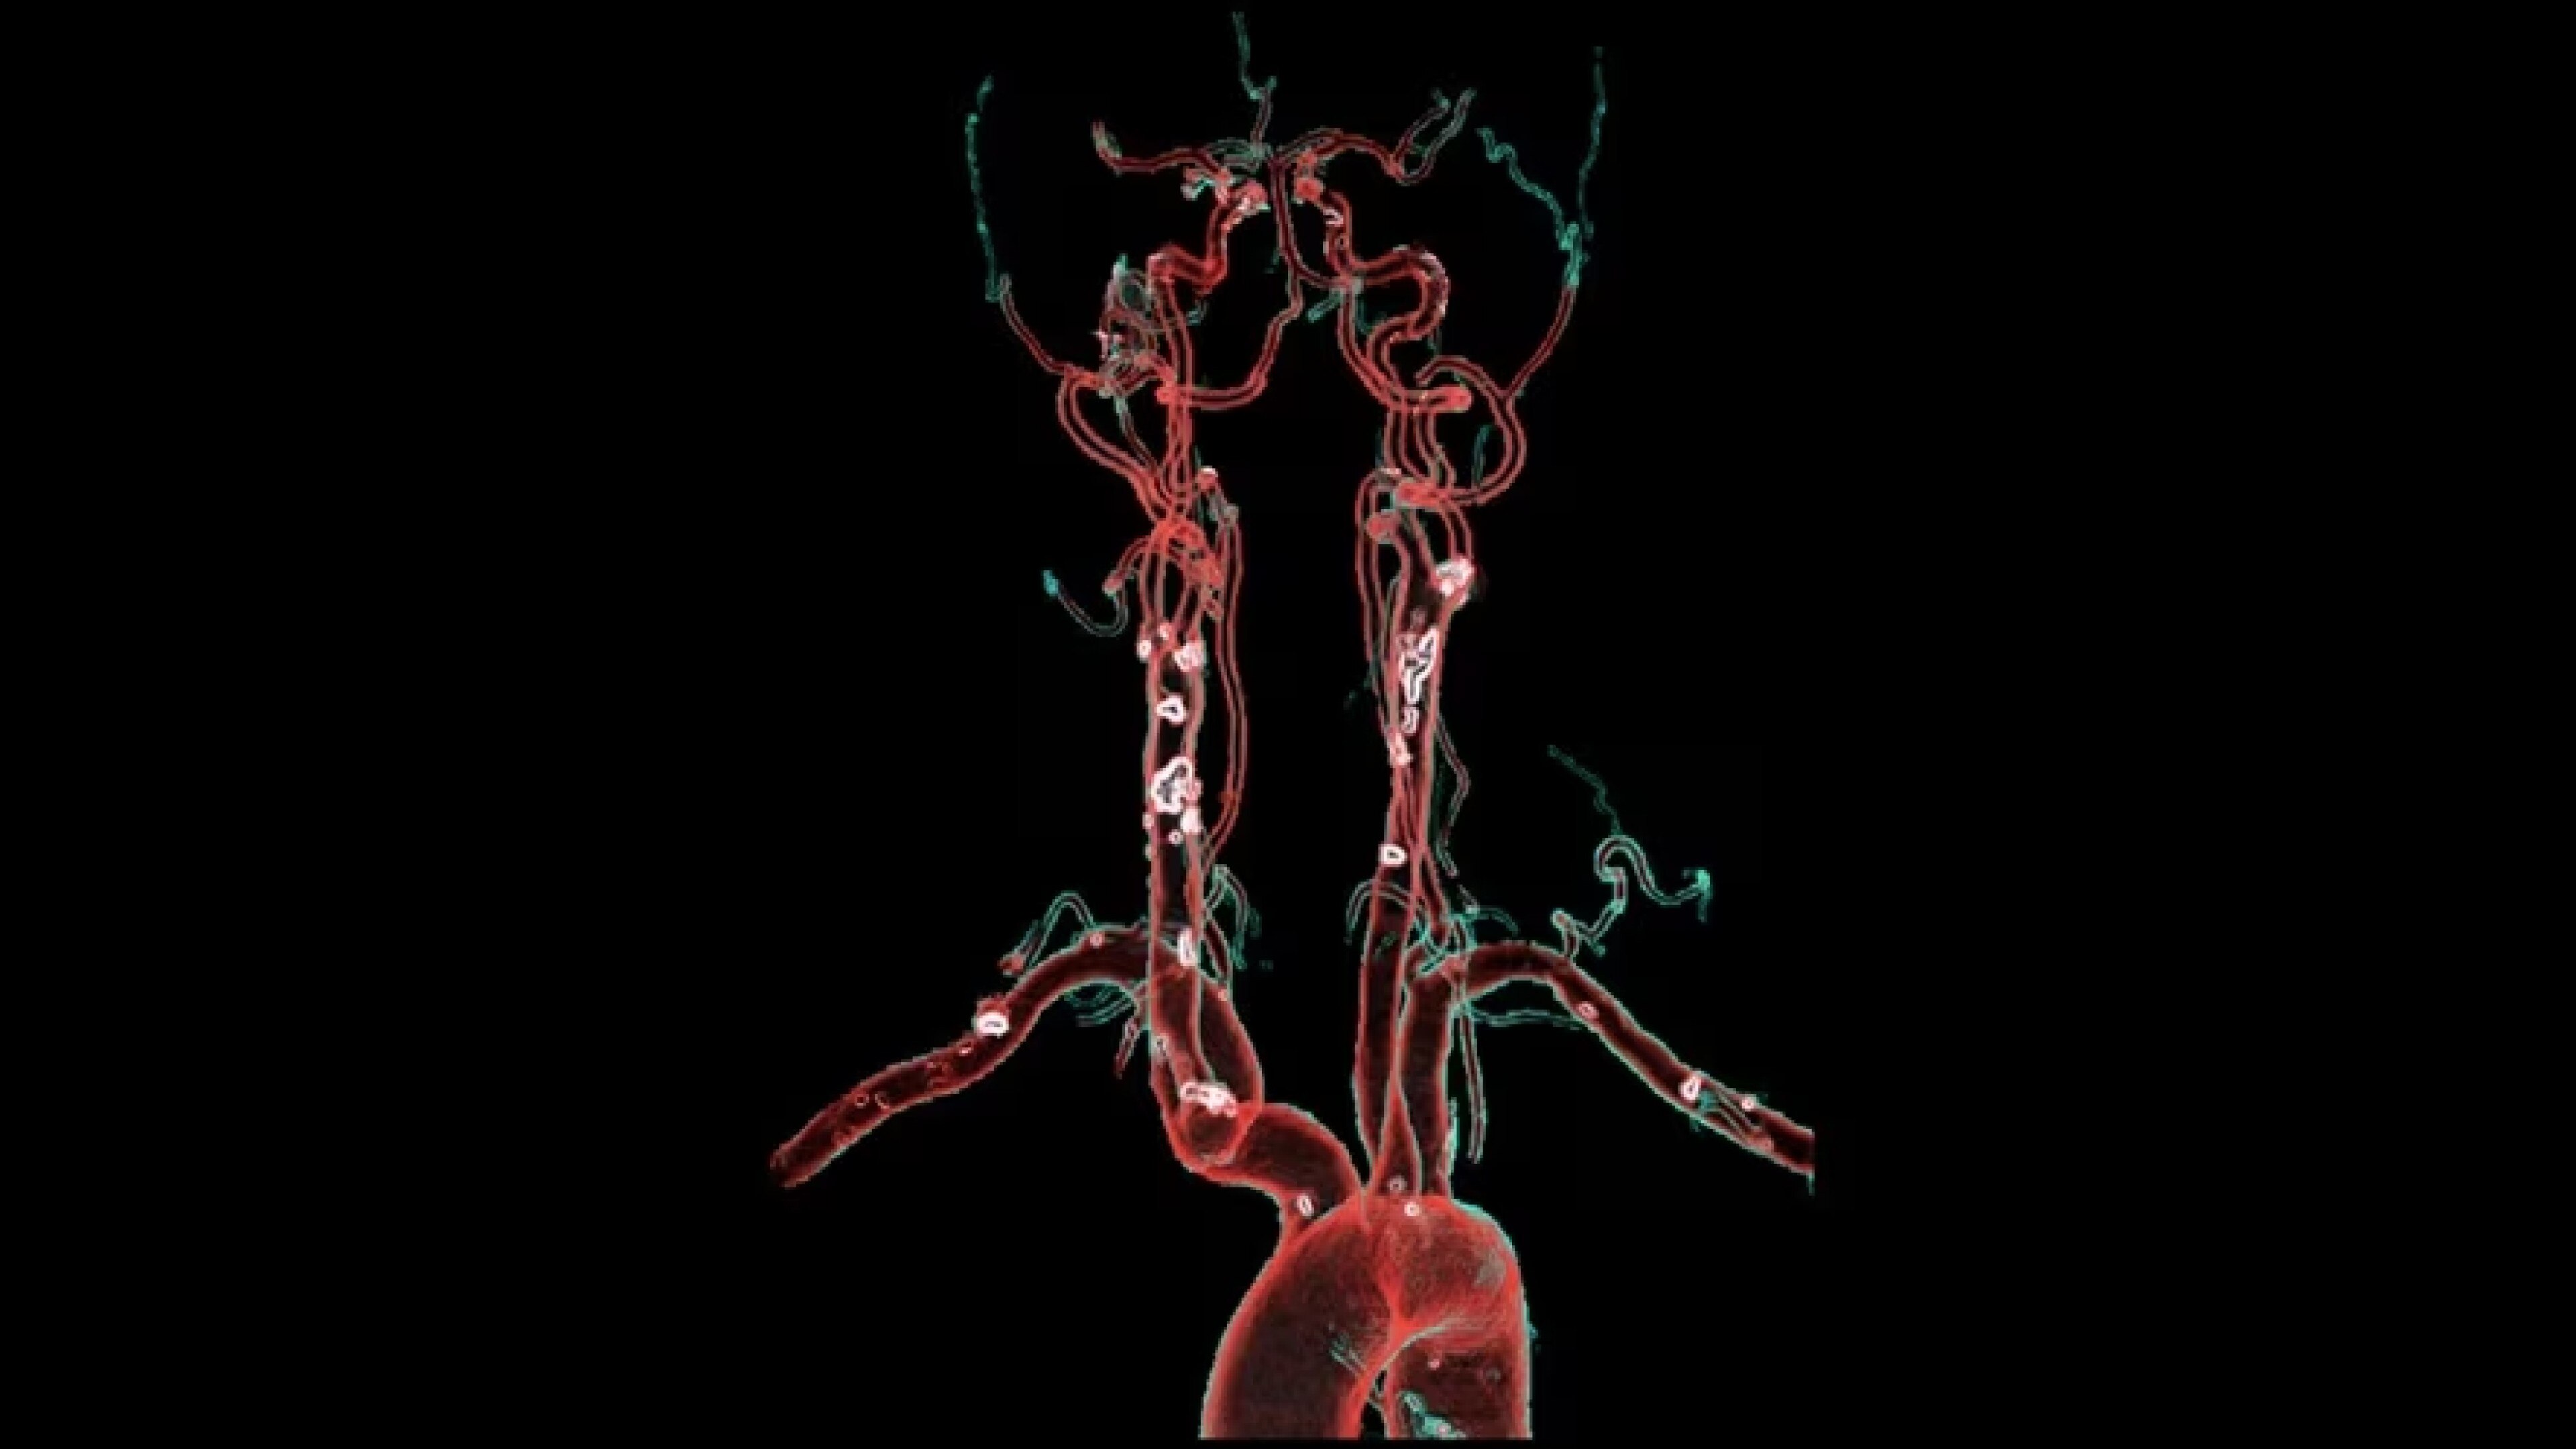

Autobone & VesselIQ Xpress

Fast and efficient vessel analysis from CT Angiography exams.

Automated detection of aorta and illiacs with auto-labeling of vessels

Comprehensive stenosis measurement and plaque analysis of any vasculature

• Automated real-time fast tracking for all vasculature.

• Automated detection of aorta an illiacs with auto labeling of vessels.